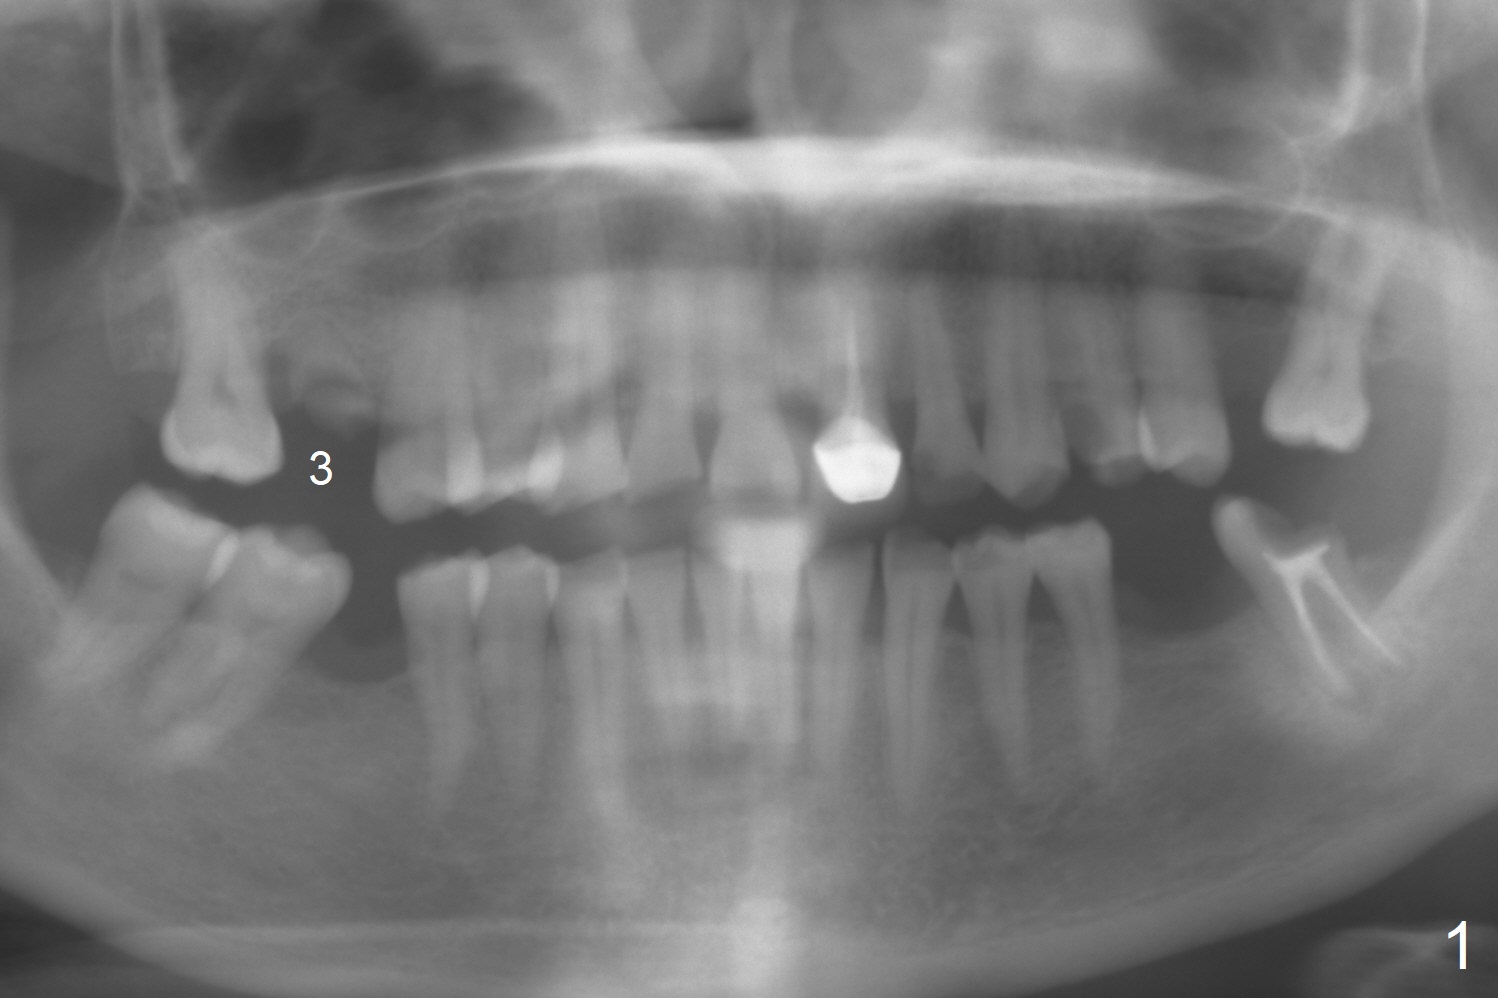

A 45-year-old woman has poor dentition due to dental phobia (Fig.1).  The tooth #3 has residual roots (Fig.2 *).  The initial depth will be 9 mm with starter drill, 2 mm drill (parallel pin, PA) and 3.2 mm Magic Drill (Fig.3).  Use 4x11 mm dummy implant for sinus lift for the last 2 mm.